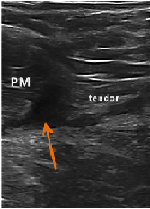

Case Report: Platelet Rich Plasma Injection Used as Treatment of High-Grade Partial Pectoralis Muscle Tear in Division I Football Player

Guy W. Nicolette, MD, CAQSM*; Kristin Farrell, MS ATC